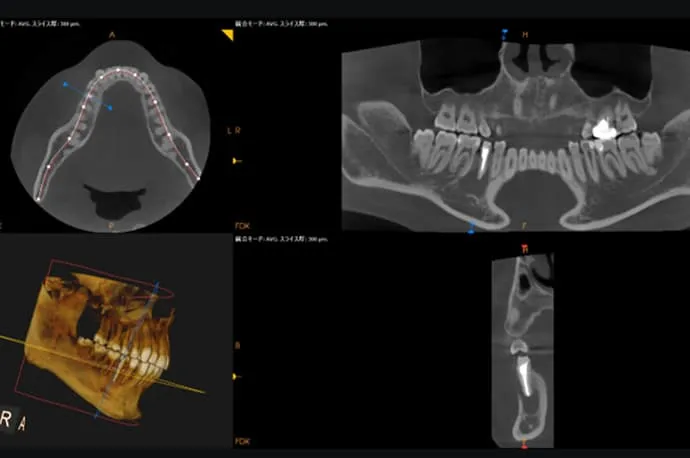

根尖部(根の先)の化膿の診断

歯の根の先が化膿しているかどうかの診断は、歯髄の診断と比べると比較的行いやすく、主にレントゲン検査を用いて確認します。

当院では、すべての患者さまにCT撮影を無料で実施しています。これにより、まだ痛みが出ていない段階の化膿や、通常のレントゲンでは見つけにくい小さな病変まで確認することが可能です。